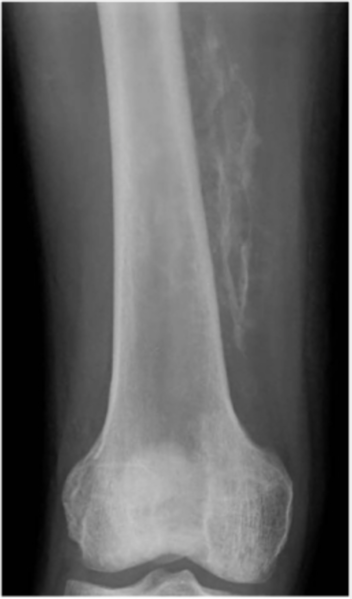

Plain radiograph taken two months after injury demonstrates irregular calcification located along muscle on medial aspect of right thigh. Diagnosis was myositis ossificans. Kim SY, Park JS, Ryu KN, Jin W, Park SY. Various tumor-mimicking lesions in the musculoskeletal system: causes and diagnostic approach. Korean J Radiol (2011)

| current | 01:11, 30 August 2016 | ![]() | 514 × 874 (286 KB) | Jstevenson (Talk | contribs) | Plain radiograph taken two months after injury demonstrates irregular calcification located along muscle on medial aspect of right thigh. Diagnosis was myositis ossificans. |